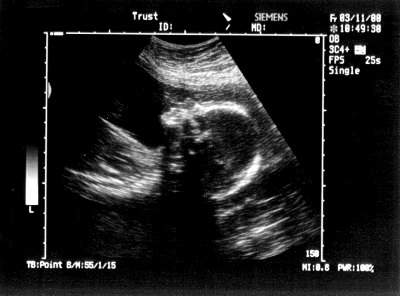

صورته في الاسبوع التاسع عشر